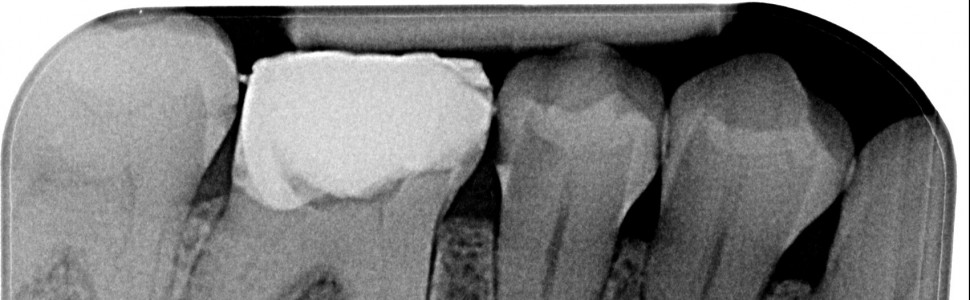

W pracy przedstawiono leczenie endodontyczne zęba 46 z przewlekłym ropnym zapaleniem tkanek okołowierzchołkowych skupiając się na istotnych etapach, takich jak opracowanie kanałów, dezynfekcja z użyciem ultradźwięków i dokładna obturacja. Podkreślono wagę skutecznego płukania kanałów jako czynnika kluczowego dla uzyskania pozytywnych rezultatów w leczeniu endodontycznym.

The article presents endodontic treatment of tooth 46 with chronic purulent inflammation of the periapical tissues, focusing on important stages such as canal preparation, disinfection using ultrasound, and precise obturation. The importance of effective canal rinsing was emphasized as a crucial factor for achieving positive outcomes in endodontic treatment.